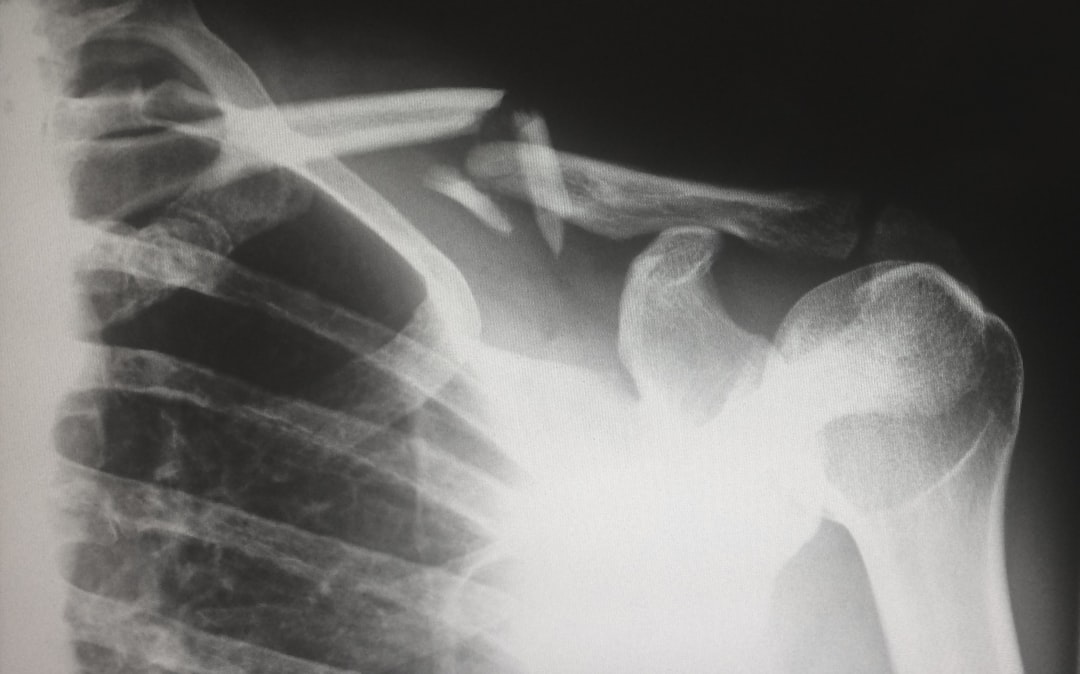

Omuz ağrısı, omuz eklemi, kemikler, kaslar, tendonlar veya bağlardaki rahatsızlık nedeniyle ortaya çıkan bir şikayettir. Bu eklem, kürek kemiği, köprücük kemiği ve üst kol kemiğinin (humerus) birleşimiyle oluşur. Omuz ağrısı, bazen boyundan yayılan bir gerginlikten kaynaklanabilirken, bazen de eklemin kendi iç yapısındaki ciddi bir problemden kaynaklanabilir.

Omuzun karmaşık yapısı, onu dört ana kas ve tendon grubundan oluşan “Rotator Manşet” ile destekler. Bu manşet, kolunuzu kaldırmanıza ve döndürmenize olanak tanır. Rotator manşet hasar gördüğünde veya iltihaplandığında, günlük hayatınızın ne kadar etkilendiğini anlarsınız.

- Ani Şiddetli Ağrı: Özellikle bir travma (düşme, kaza) sonrası aniden başlayan dayanılmaz ağrı.

- Gözle Görülür Şekil Bozukluğu: Omuz ekleminin yerinden çıkmış gibi görünmesi (omuz çıkığı).